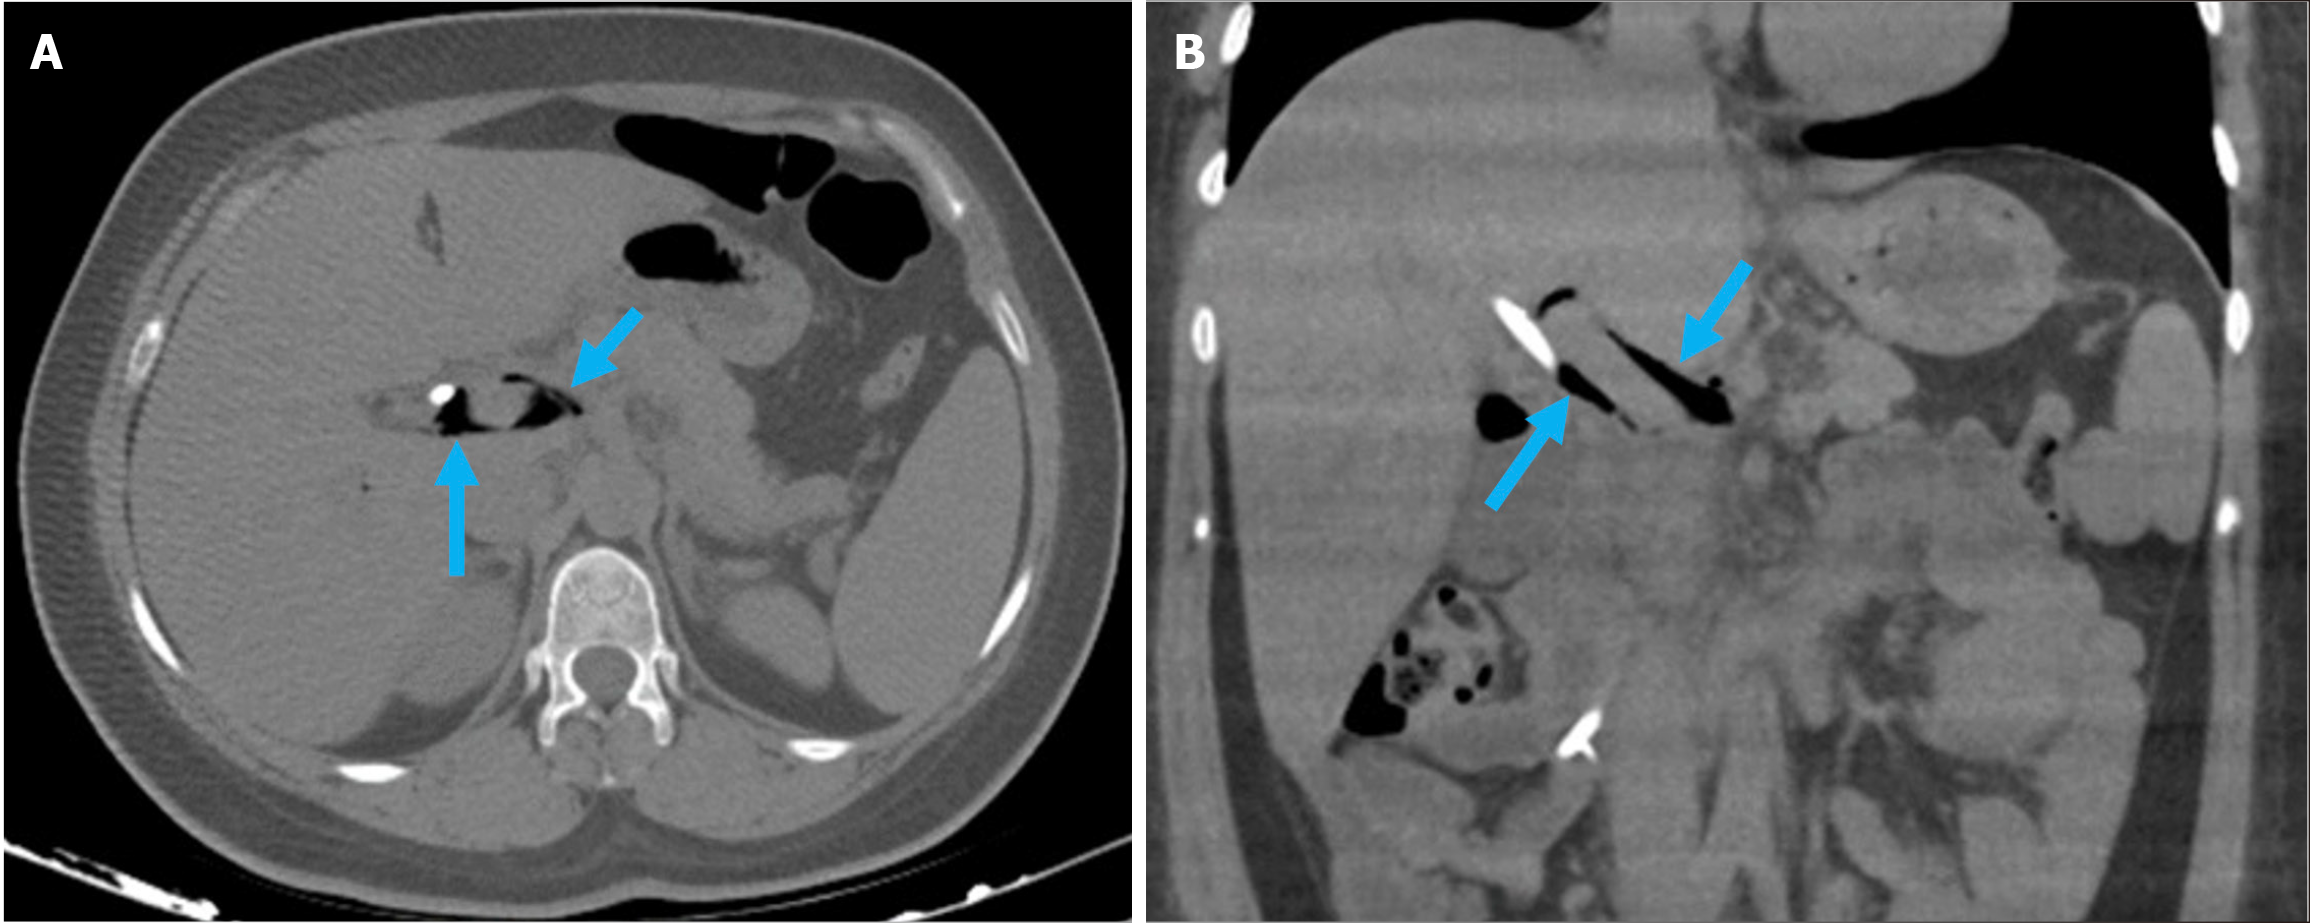

Acute duodenal wall hemorrhage appears as an area of high-attenuation wall thickening on imaging. The attenuation decreases as the hemorrhage evolves and often forms a pseudocapsule. Hyperattenuating blood can be seen within the CBD and the duodenal lumen in cases of intraluminal bleeding. Arterial phase acquisition with vascular window settings and maximum intensity projection reconstruction demonstrate active contrast extravasation in the duodenum (Figures 9 and 10)[37,61,62].

Figure 10

Figure 10  Hemobilia. A and B: Axial (A) and coronal (B) noncontrast computed tomography images depicted findings of hemobilia in an 84-year-old female patient with coagulopathy who presented with abdominal pain and a drop in hemoglobin following endoscopic retrograde cholangiopancreatography. Dilatation of the common bile duct with hyperattenuating intraluminal material consistent with hemorrhage was observed (yellow arrows). Hyperdense gallstones were also visible within the gallbladder (blue arrow).